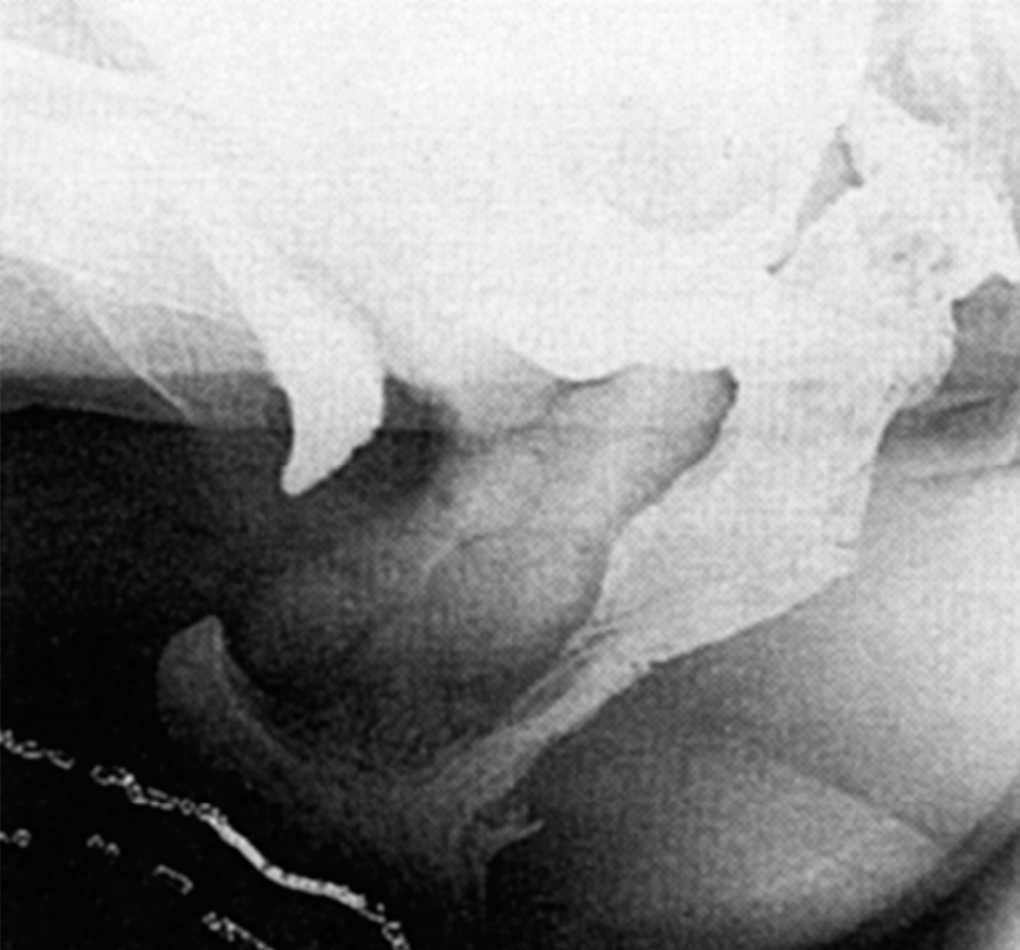

Las pacientes ingresaron la tarde anterior para la preparación mecánica del colon. Se instauró pauta de profilaxis antitrombótica y dosis única de antibióticos previa a la cirugía. Se realizó anestesia locorregional y sedación en todos los casos. En posición de Lloyd-Davis se realizó una colpotomía longitudinal posterior y disección de todo el espacio rectovaginal, desde esfínteres anales hasta fondo de saco vaginal posterior; lateralmente se disecó hasta los haces laterales del músculo puborectalis. En el caso del enterocele hay que añadir una disección de todo el saco peritoneal y resección de éste. Posteriormente, y después de hacer una hemostasia adecuada para evitar hematomas con la colocación de una malla, se colocó una malla de Marlex (polipropileno, CR Bard Inc., Billerica, MA) en todo el espacio rectovaginal suturada con puntos de polipropileno para evitar su migración después de la intervención con los movimientos defecatorios de la paciente y hasta que su integración en los tejidos fuera absoluta (fig. 2). Se realizaron 7 levatorplastias anteriores durante el comienzo de la técnica, y no se realizaron posteriormente en la serie de pacientes debido a la gran diastasis de haces del músculo puborectalis y la imposibilidad de su aproximación. En 4 pacientes con incontinencia fecal de origen obstétrico se realizó esfinteroplastia sincrónica con la colocación de la malla.

Fig. 2. Malla de polipropileno suturada al tabique rectovaginal.